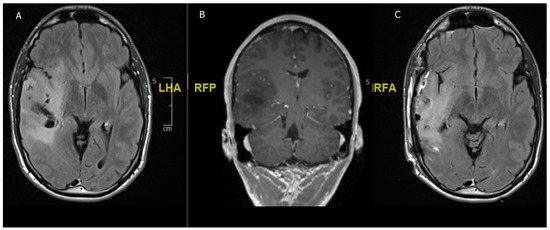

Figure 4. An 8 year-old girl undergoing treatment for congenital scoliosis. (A) MRI head carried out in the setting of her scoliosis work-up showed an incidental finding of a T2 hyperintense cerebellar lesion (B) Interval scan after 6 months showed a spontaneous regression of the lesion. No resection or biopsy was attempted.

The phenomenon of spontaneous regression has been described in some reports on pLGG but it is basically non-existent in adults. In a case series by Ogiwara, a total of 30% of all partially resected cerebellar pLGG demonstrated spontaneous regression over a median time of 11.9 months [99]. Similar rates (32.5–48%) of spontaneous regression or arrested growth have been described in other case series of cerebellar pLGG [100,101] (Figure 4). This could warrant the decision not to chase the tumor into eloquent regions, such as the peduncle or parts of the brainstem, to avoid postoperative morbidity [99]. Telomerase shortening and the induction of apoptosis are hypothesized to cause growth arrest and the telomere length could offer some prognostic value in pLGG; however, further studies are needed to elucidate this matter [102].

Spontaneous regression is observed in around one third of pLGGs but not in aLGG. This warrants the concept of avoiding radical tumor resection in eloquent regions in children with suspected or confirmed LGG.